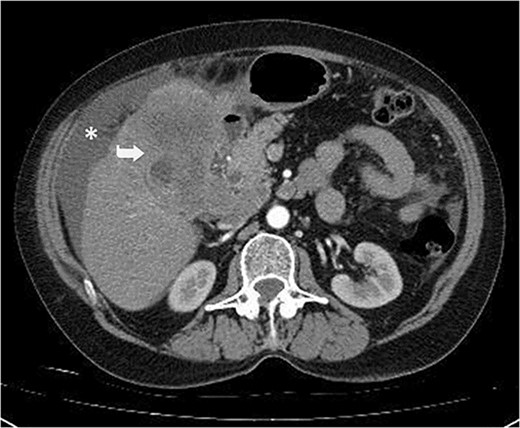

A 59-year-old woman presented with complaints of abdominal pain and abdominal distension for about a month. There was no known systemic disease and no history of previous abdominal surgery. It was learned that the patient had been admitted to the emergency department in another center one month ago with the current complaints and was discharged after medical treatment. Physical examination at the time of admission revealed abdominal distension and diffuse minimal tenderness with no signs of peritoneal irritation. Laboratory tests revealed that hemogram and biochemical parameters were within normal limits, but one of the tumor markers, the patient’s CA 19-9 level was significantly elevated at 855 U/ml (normal range: 0–37 U/ml). Contrast-enhanced CT scan showed a 10×10 cm heterogeneous mass in liver segments 4B-5, extending to segment 6, and free fluid adjacent to the liver and irregular liver contours. Borders of the gallbladder could not be seen. Soft tissues forming nodular mass formation were detected on the omental surfaces (Fig. 1). Computed tomography examination performed at the center where the patient was admitted as an emergency one month ago revealed hypodense lesions measuring 10×8 cm in size in the left lobe of the liver, protruding into the inferior perihepatic area, and 3.5 cm in diameter in segment 5 of the right lobe with no significant contrast enhancement after intravenous injection of contrast material. Perihepatic ascites was not detected and gallbladder size, wall thickness and lumen were normal (Fig. 2). In the light of the radiologic findings, a pre-diagnosis of progressive gallbladder malignancy was considered. The patient was hospitalized in the General Surgery ward for further investigation and treatment. Because of the presence of ascites causing abdominal distension, a percutaneous ascites drainage catheter was placed and 5000 cc ascites drainage was performed. Cytologic examination of the ascitic fluid revealed cell groups with unclear three-dimensional cytonuclear detail among lymphocytes and mesothelial cells with reactive atypia and malignancy was considered suspicious. With the current radiologic and cytologic findings, inoperable metastatic gallbladder carcinoma was considered. Medical treatment was decided by the multidisciplinary oncology council and 18G needle tru-cut biopsy was performed from the 10×10 cm mass adjacent to the gallbladder for definitive tissue diagnosis and adjuvant treatment planning. Histopathologic examination revealed a diagnosis of neuroendocrine carcinoma (NEC) (Fig. 3). Immunohistochemical examination revealed strong staining of tumor cells with CD56 (Fig. 4), synaptophysin (Fig. 5), chromogranin A (Fig. 6), and Ki67 index was >90% (Fig. 7). Weak staining was observed with CK19, CK7, and CDx2, but no staining was observed with CEA and CK20. Morphologic findings were compatible with small cell type. Etoposide and cisplatin chemotherapy was planned but the patient’s general condition deteriorated progressively. The patient couldn’t start chemotherapy and unfortunately resulted in mortality on the 20th day of hospitalization.

Hypodense lesions in the left lobe of the liver, 10×8 cm in size, protruding into the inferior perihepatic space and 3.5 cm in diameter in the right lobe segment 5 with no significant contrast enhancement after intravenous contrast material injection (Arrow).